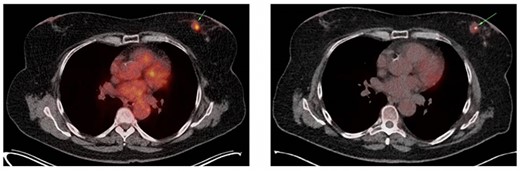

A 64-year-old female was diagnosed with a left-sided cT2N1M0 lobular breast carcinoma for which she was treated with neoadjuvant chemotherapy. Partial radiological response was observed (Fig. 1) and an oncoplastic breast-conserving surgery was performed. After pathological examination, an ypT2N1a(sn) TNM classification (8th edition UICC), ER-positive (100%), PR-negative (0%) and HER2-negative, was found, and adjuvant radiotherapy and hormone therapy were indicated.

(A) Axial slice of a thoracic PET/CT showing the lobular carcinoma in the left mamma (green arrow) before neoadjuvant chemotherapy. This PET/CT was performed 7 months prior to ER presentation. (B) Axial slice of a thoracic PET/CT showing the lobular carcinoma in the left mamma (green arrow) after neoadjuvant chemotherapy with partial response. This PET/CT was performed 7 weeks prior to ER presentation.